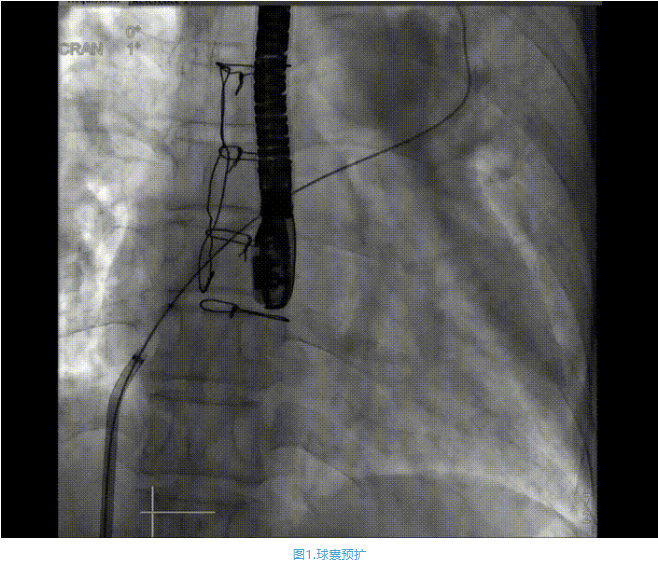

術(shù)中首先在局麻下穿刺股動脈、股靜脈,完成心導(dǎo)管檢查評估后轉(zhuǎn)為全麻,在食道超聲引導(dǎo)下穿刺房間隔,穿刺成功后將加硬導(dǎo)絲送入左上肺靜脈建立軌道,根據(jù)患者病情行球囊預(yù)擴(kuò)張后植入6mm孔徑房間隔造孔支架,經(jīng)透視及食道超聲評估支架左右盤展開良好,夾持于房間隔兩側(cè),固定穩(wěn)定、位置良好,食道彩超顯示房水平右向左為主分流,分流孔直徑符合預(yù)期大小,心導(dǎo)管檢查評估達(dá)到預(yù)期效果,釋放造孔支架。術(shù)后12h患者下床活動,恢復(fù)順利,擬于近日完善術(shù)后評估后出院。